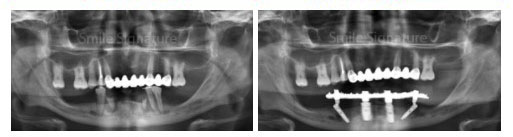

- Checking of Implants. On your return trip. We perform x-ray imaging to verify successful healing before taking precision impressions for your permanent set of dentures.

- Fitting of Denture. Your choice of bar, ball, or locator attachments is installed over the implants, and your final dentures are securely fitted.

During your return visit, your dentist takes a panoramic x-ray to check if the implant posts is successfully integrated with the jaw bone. Your dentists takes tooth impressions to construct your permanent dentures in the dental labs. On its delivery, locators, balls or bars are screwed into the implant posts with the dentures snapped over securely over.